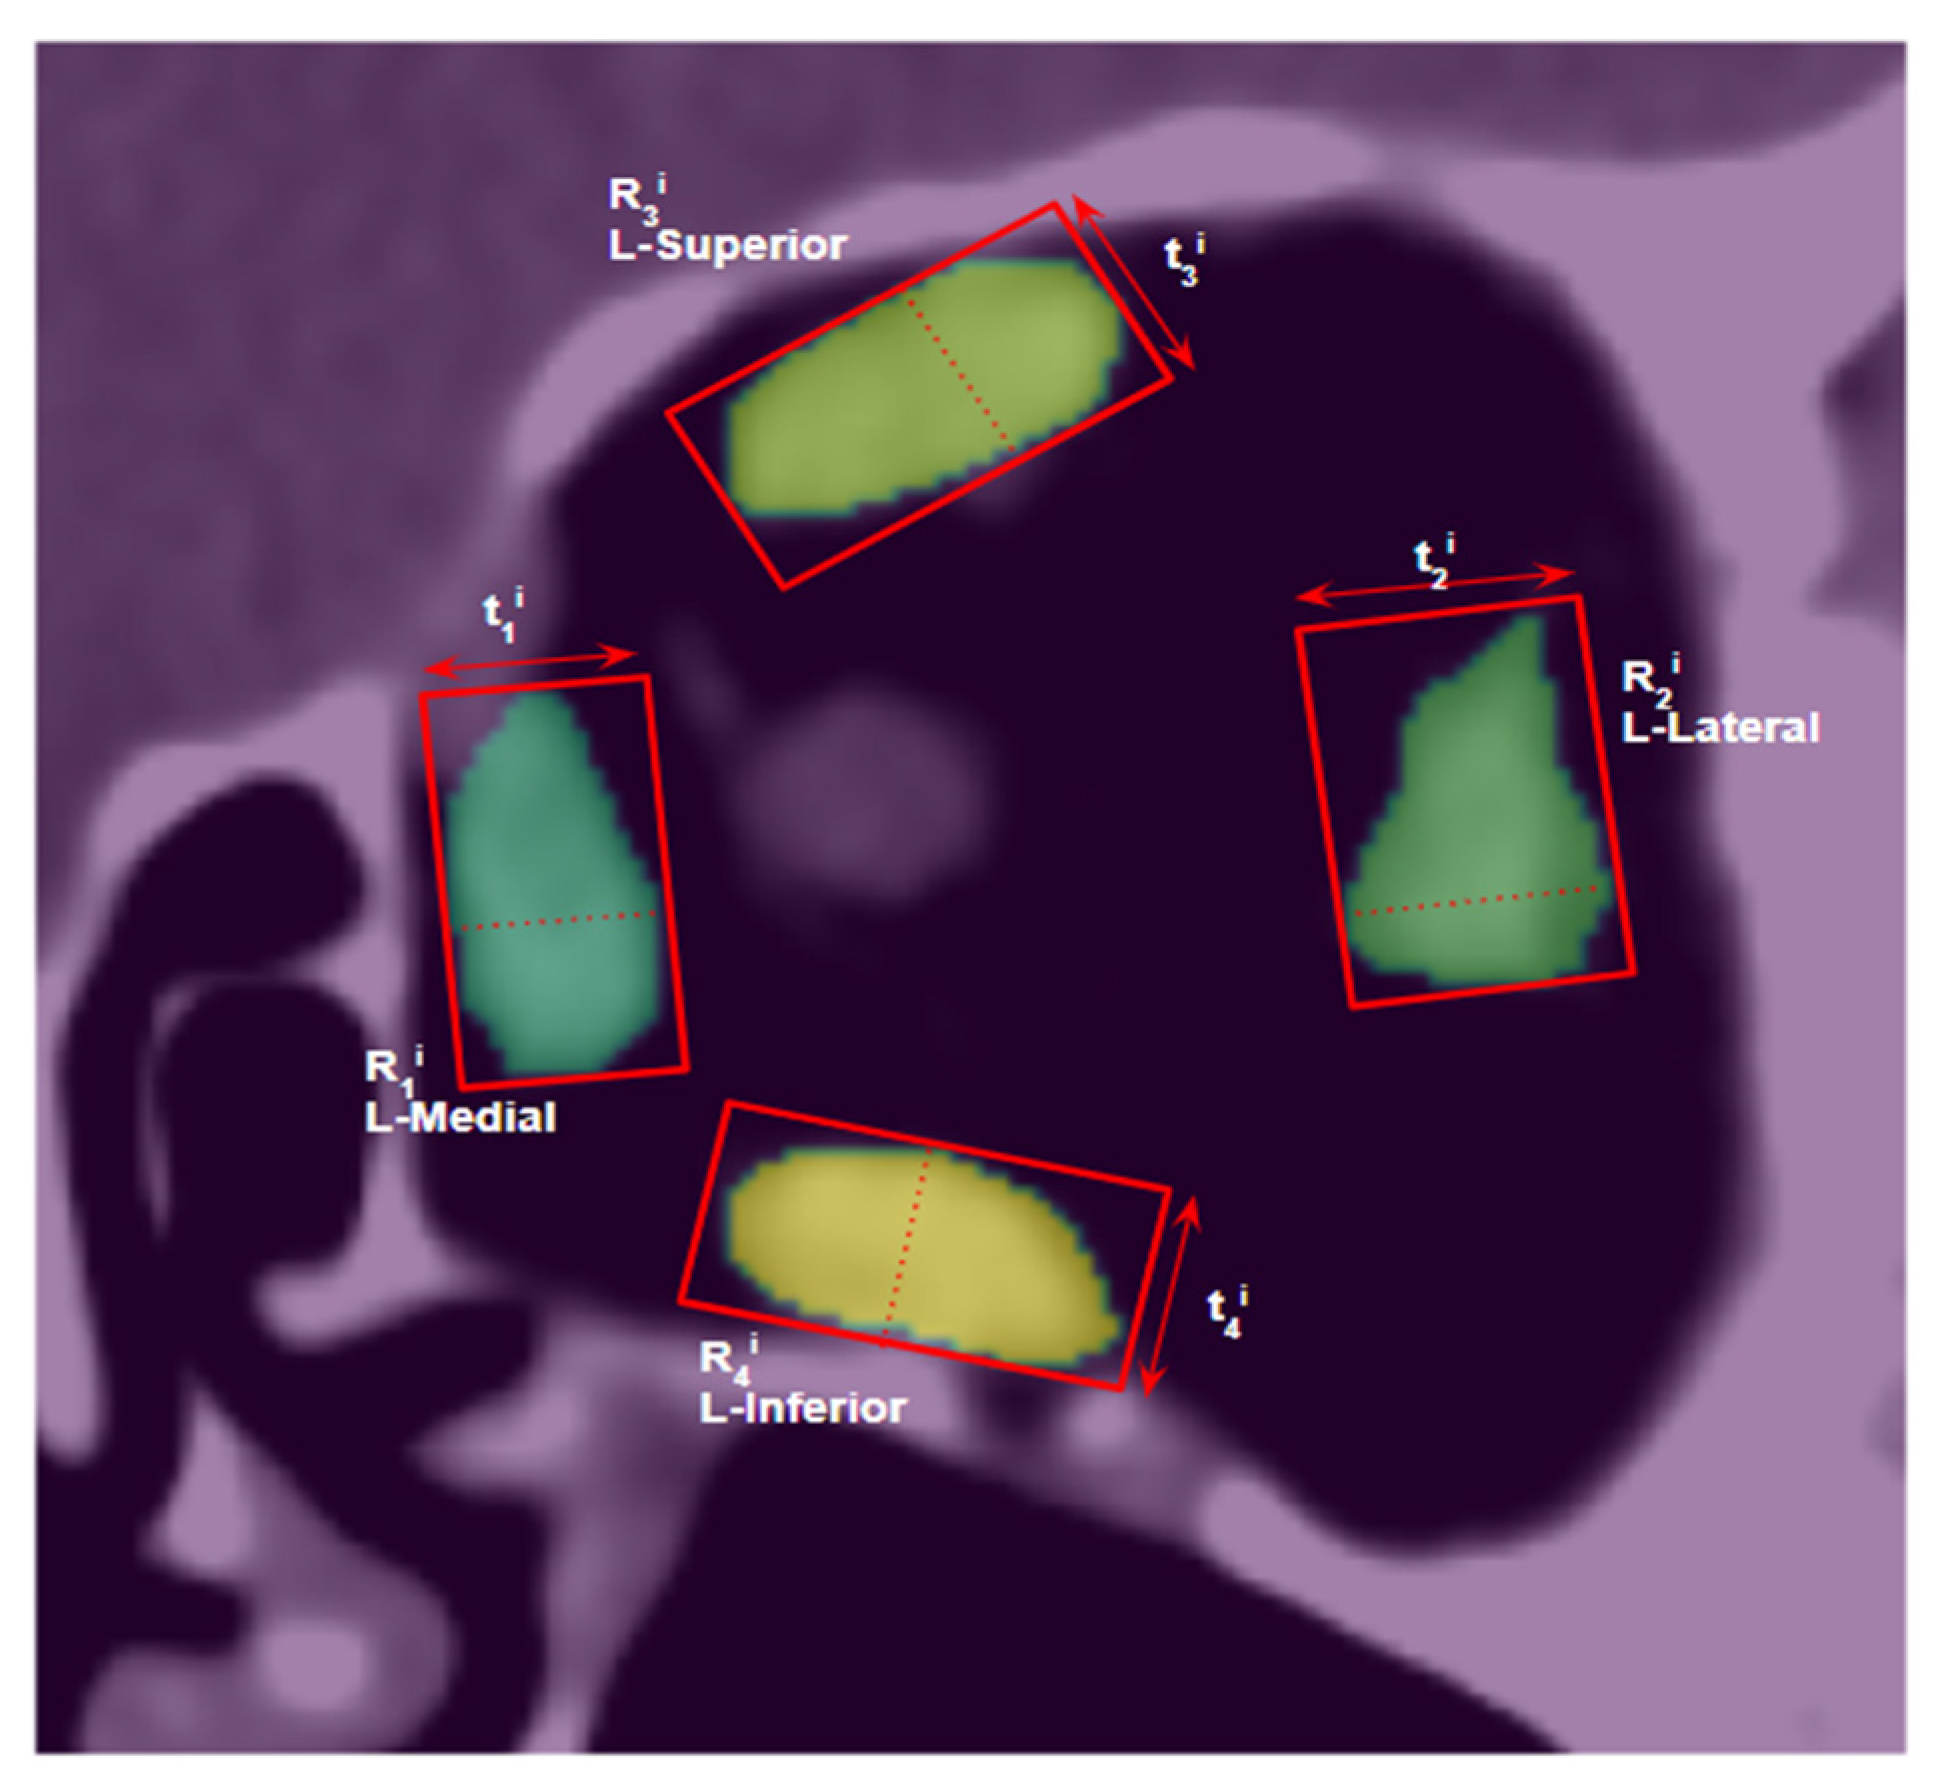

2.8. Muscle Size Measurement